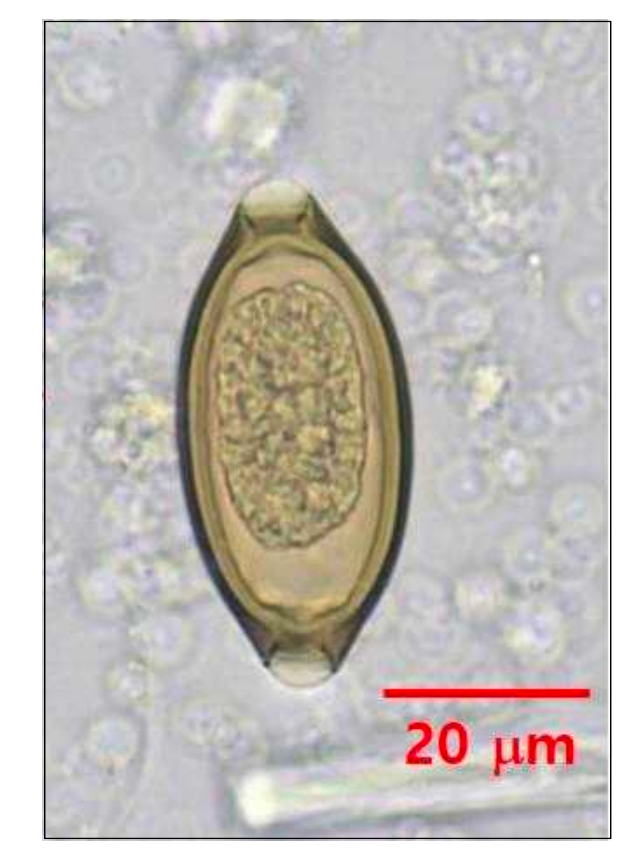

• 충란은 술통형으로 양쪽에 투명한 플러그가 존재한다. (사진자료 참조)

편충